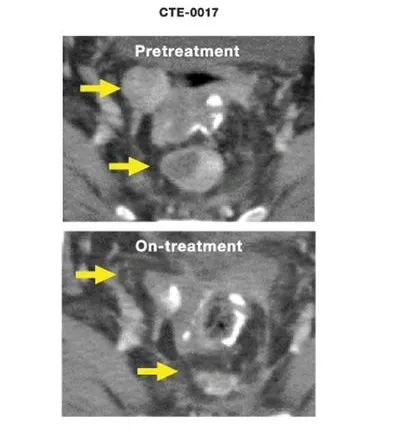

![]()

图示经过几周治疗后,患者病情得到明显控制